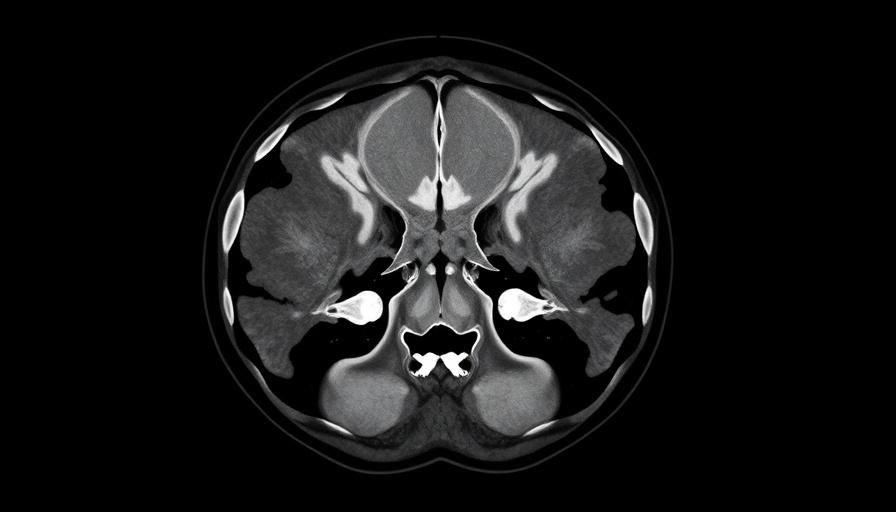

IMRT is a form of radiation therapy that enhances precision in delivering radiation doses while reducing exposure to surrounding healthy tissues. This approach has become the benchmark for treating head and neck cancers like OPSCC. On the other hand, IMPT uses protons to target tumors more accurately, purportedly minimizing damage to healthy tissue. Despite the theoretical advantages of proton therapy, including its capacity to spare healthy tissue, the IMPT failed to outperform IMRT in significant areas, such as late side effects and quality of life scores, as per Dr. David Thomson’s findings.

The TORPEdO trial included 205 patients, revealing results that surprised many in the oncology community. Notably, patients undergoing IMPT encountered similar rates of feeding tube reliance and weight loss when compared to their IMRT counterparts. For instance, 17.6% of participants in the IMPT group experienced feeding tube use or severe weight loss, compared to just 6.8% in the IMRT group. Such statistics indicate that while IMPT appears to have the edge in theory, patients receiving IMRT reported a better quality of life overall.